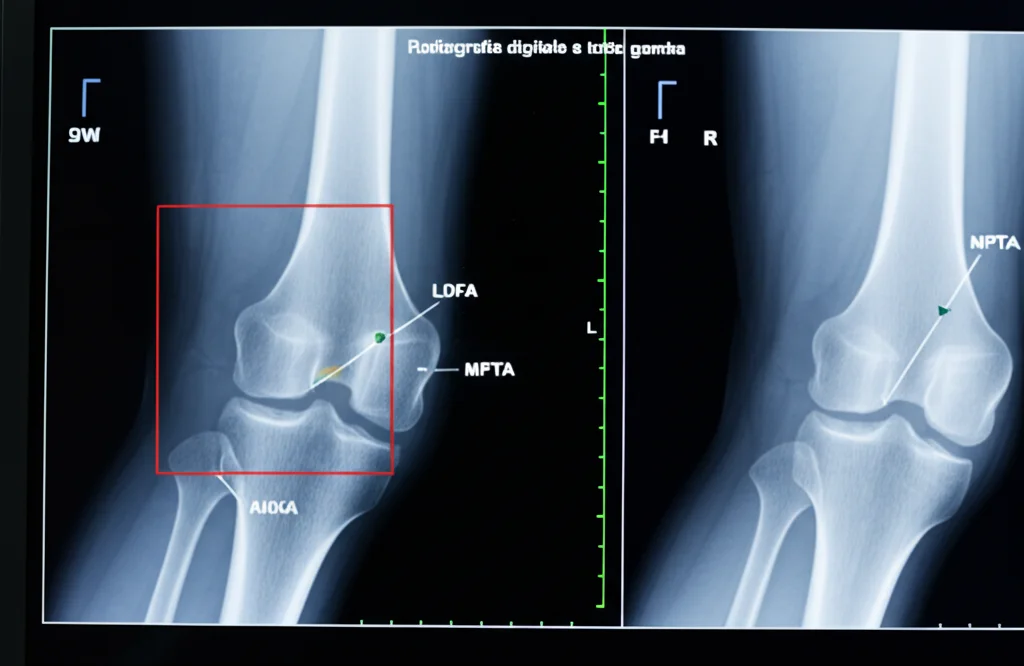

Ed è qui che entra in gioco l’angolo aHKA. Cos’è esattamente? È un indicatore della morfologia ossea “costituzionale” del ginocchio, calcolato usando misurazioni specifiche prese su radiografie a gamba intera: l’angolo laterale distale del femore (LDFA) e l’angolo mediale prossimale della tibia (MPTA). La formula è: aHKA = 180° – LDFA + MPTA.

La cosa geniale dell’aHKA è che si basa esclusivamente su punti di riferimento ossei. Questo significa che, a differenza dell’angolo mHKA preoperatorio (che riflette l’allineamento attuale, influenzato dal consumo della cartilagine e dalla lassità legamentosa), l’aHKA ci dà un’idea dell’allineamento “originale” della gamba, prima che l’artrosi facesse i suoi danni. È indipendente dal restringimento dello spazio articolare e dalla posizione del paziente durante la radiografia (in piedi o sdraiato), rendendolo potenzialmente più riproducibile e meno soggetto a errori.